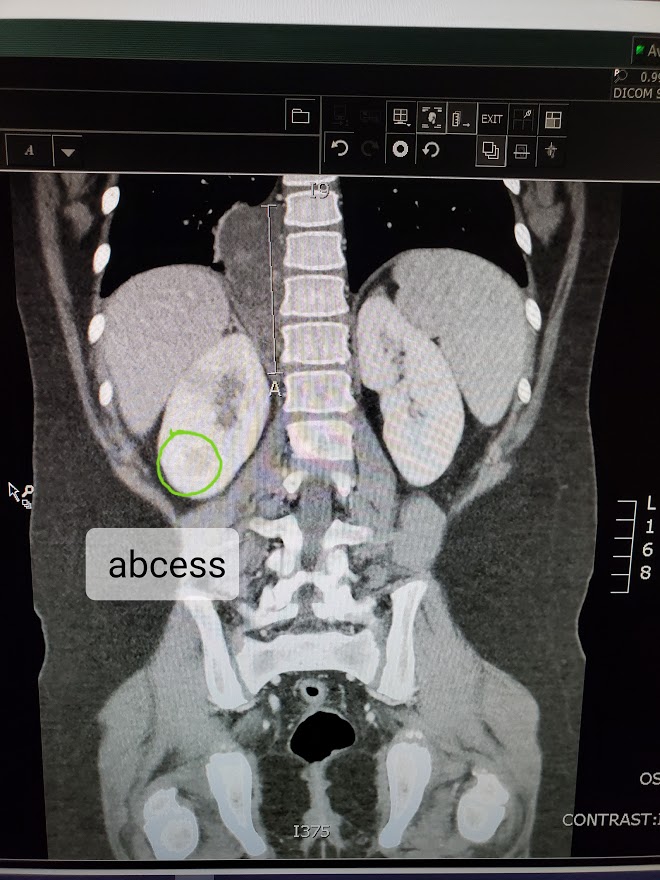

We rushed our sweet Savannah to the ER last night with a high fever and abdominal pain, sure that it was appendicitis. A CT scan revealed that her RT kidney was severely infected and that an abscess on the Kidney had been found. To our relief, her appendix looked fine and our little girl would not be rushed into surgery. After discussion with her ER doctor, it was decided that a consult with the children’s hospital would be wise to see if further analyzing or treatment for the abscess would be needed.

The ER at the Children’s Hospital was empty at such an early time of morning. We arrived around 12:30am where she was checked in with a fever of 105.3. She was so tough and so brave and so tired. Again, we waited. When the ER doctor came in, it was nearly 2:30 in the morning. Savannah was in deep sleep and Brannick and I were so tired and anxious to get her admitted and settled into her hospital bed. I don’t recall his name, or even much of what he looked like but I do remember exactly what his voice sounded like. I am not sure I will ever forget the sound of his voice. He informed us that the radiologist had reviewed her CT and had found no abscess on her Kidney. Yes, there was indeed a large amount of infection on and around her Kidney but there would be no need for the draining of an abscess. I looked at Brannick and we both sighed in premature relief. I asked how soon we could get her moved to a room so she could settle and I immediately knew that something was wrong. His body language. His eyes behind the mask.. The tone of his voice. “There is no abscess, but the radiologist did find a large mass in Savannah’s abdomen along her spine behind her RT kidney. The most likely diagnosis at this point is a Neuroblastoma.” I gasped in my mask and I could not hold back the tears. I knew that word. I know what that means. I couldn’t believe what I was hearing. Brannick held my hand and we both tried to listen as shock set in. “We will need to admit her to the Oncology floor. A team of Oncologists and Surgeons will review her case and meet with you tomorrow morning. I am so sorry.”